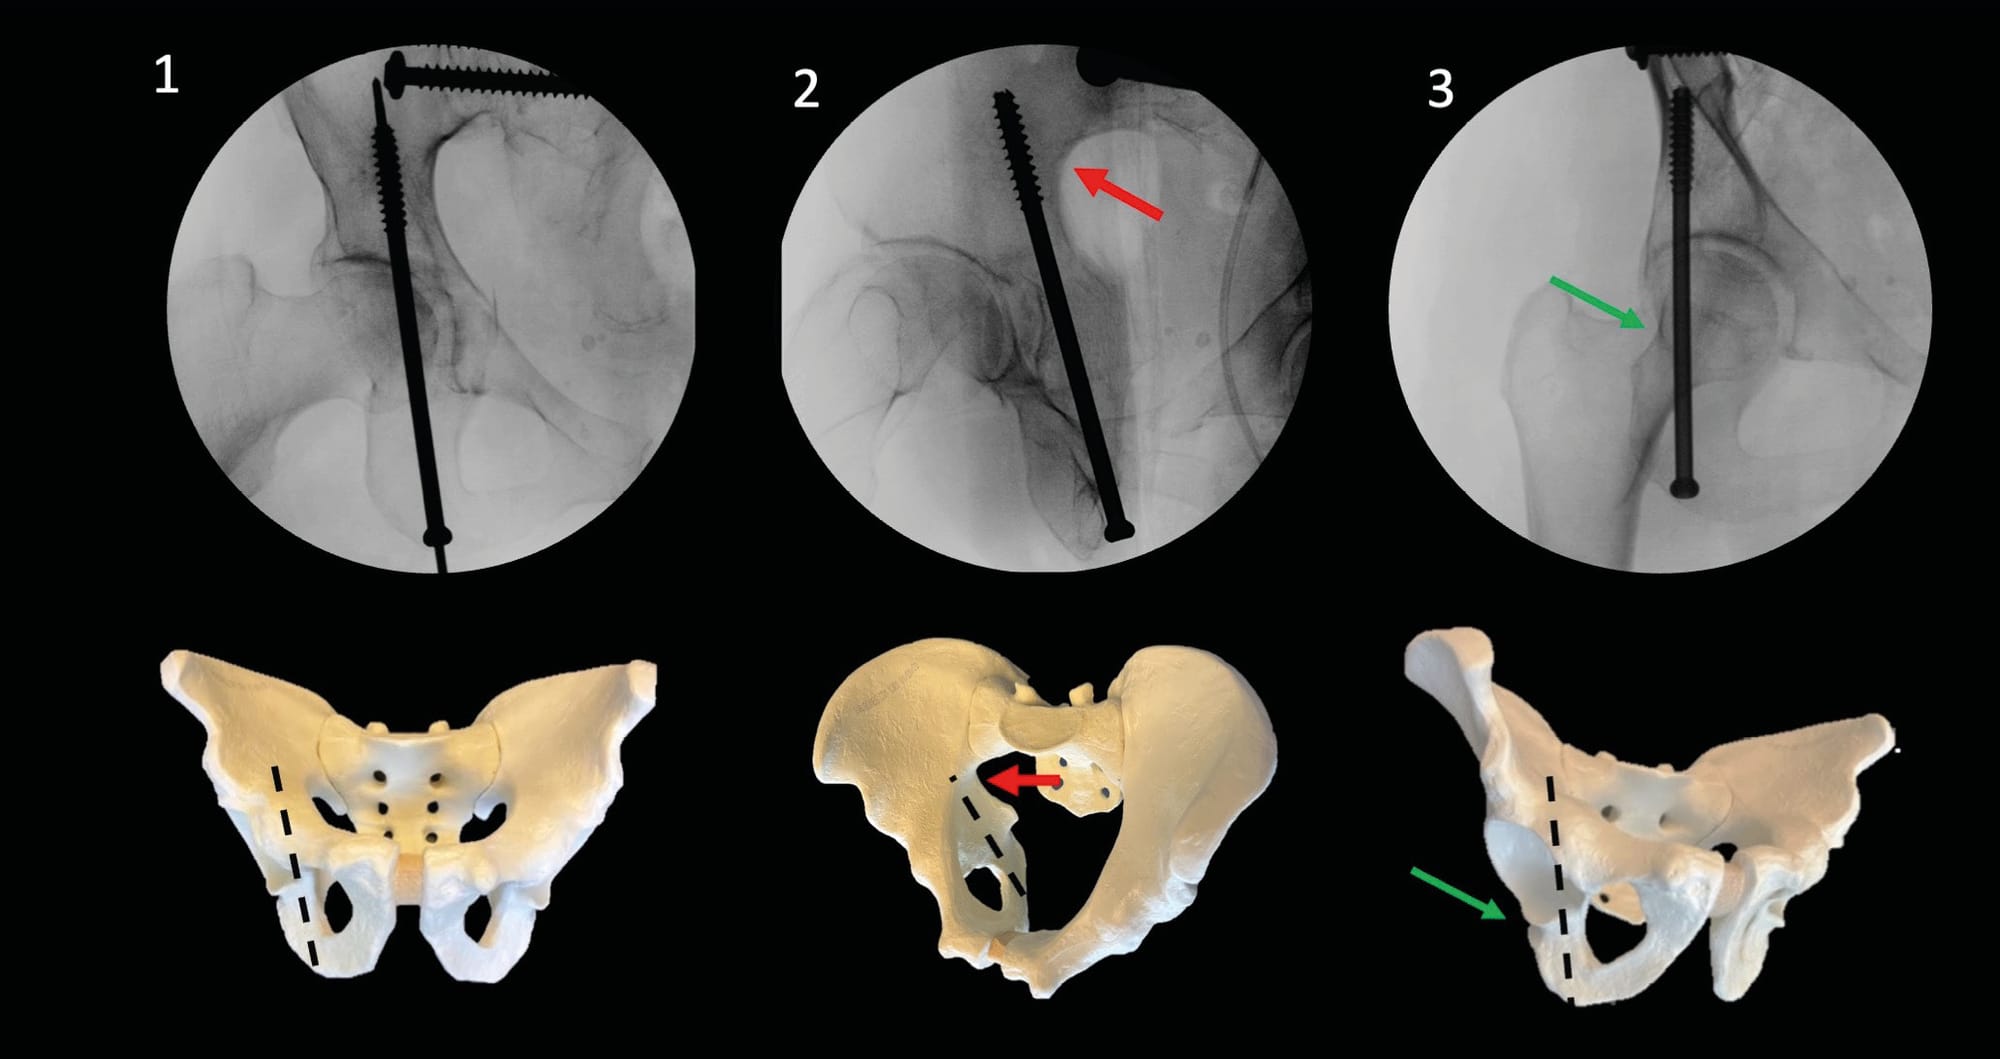

The lumbosacral junction is one of the most variable regions of the spine. Although the total number of vertebrae in the thoracolumbosacral region remains constant, sacral fusion levels differ. It is important to look for radiographic characteristics of dysmorphism, as this variation significantly alters the upper sacrum and therefore the screw corridors (Figure 4). As comprehensively described by Tonetti et al. [1] Tonetti J, van Overschelde J, Sadok B, Vouaillat H, Eid A. Percutaneous ilio-sacral screw insertion. Fluoroscopic techniques. Orthop Traumatol Surg Res 2013;99:965–72. https://doi.org/10.1016/j.otsr.2013.08.010., the following characteristics should be sought:

Depending on the injury being treated, fixation can be either ilio-sacral or trans-sacral, highlighting the crucial importance of careful injury analysis and rigorous procedure planning. In cases of sacroiliac joint disruption with significant diastasis, ilio-sacral screw fixation is preferred, as it provides a reduction vector perpendicular to the displacement. IS screw fixation can be performed at either the S1 or S2 level. However, for sacral fractures, trans-sacral screw fixation may represent an interesting option due to the perpendicular orientation of the corridor relative to the fracture site. This type of fixation can also be used in the treatment of bilateral or highly unstable injuries, such as vertical shear injuries.

The osseous corridors have been extensively described in the literature, including IS-S1 or S2, TS-S1 or S2, and even S3 in cases of dysmorphism. In non-dysmorphic sacra, only S1 and S2 corridors are accessible, as the inferior portion of the iliac tuberosity ends at the superior aspect of S3. In the presence of dysmorphism, the cranial rearrangement of sacral elements allows access to the S2 and S3 vertebrae.

Numerous studies have demonstrated the feasibility and safety of trans-sacral screw fixation at the S2 level. Although S1 is the vertebral body offering the highest bone density, it has been shown that the bone density of the posterior pelvic ring is higher in the iliac tuberosities and sacroiliac joints, providing trans-sacral fixation with better anchoring for the most unstable injuries.

These techniques can be performed in either supine or prone position; however, to minimize anesthetic complications in trauma patients, the supine position is preferred. The starting point for screw placement can be determined using a lateral view. The main fluoroscopic views used are the Inlet and Outlet views. The Inlet view shows the anteroposterior boundaries, while the Outlet view guides the caudocranial trajectory. A lateral view can be used for the entry point, but primarily to secure the trajectory in relation to the lumbosacral trunk. Finally, an Inlet + Obturator view will allow monitoring of the external table of the tuberosity and thus the length and application of the screws. (Figure 3)

For a unilateral IS screw, the starting point is slightly more posterior, with a trajectory directed upward and forward into the sacral promontory (Figure 6). A TS screw will have a more anterior entry point and a horizontal trajectory, thus allowing passage under the sacral wings and above the first foramen for a TS-S1 screw, and between the S1 and S2 foramina for a TS-S2 screw (Figure 7).

Once the appropriate direction is identified, the guide wire is advanced using power equipment. When its tip reaches the level of the foramina, the lateral view allows verification that the wire is positioned posterior to the cortical density lines, thus limiting the risk of misplacement at this level that could lead to iatrogenic injuries of the lumbosacral trunk. Similarly, along with the Inlet view, it helps ensure that the wire trajectory is not directed toward the spinal canal, which could cause cauda equina injuries. It is also recommended to maintain distance from the inferior aspect of the sacral foramina and anterior sacral landmarks. The guide wire is then advanced to the desired position. After checking the different views, the appropriate screw (usually 7.3 or 8 mm in diameter) is implanted using dedicated instrumentation. To improve fixation in the sacral wings, which often have poor bone quality, we prefer using fully threaded screws for all lesions. In cases of sacroiliac disruption, using a lag screw technique allows for compression [14] Maher M, Baldini TH, Parry JA, Mauffrey C. The potential biomechanical advantage of lag by technique screw fixation of the posterior pelvic ring. Eur J Orthop Surg Traumatol 2020;30:1045–8. https://doi.org/10.1007/s00590-020-02665-8. (Figure 4). The screw length can be verified using an ipsilateral and contralateral sacroiliac joint view (Inlet + three-quarter obturator).

Preoperative evaluation is essential to anticipate difficulties associated with posterior arch screw fixation. Pelvic version and sacral tilt can complicate the acquisition of Inlet and Outlet views. Analysis of sagittal CT scans preoperatively helps overcome these challenges by providing an estimate of the angles needed to obtain these views (Figure 8).

In the presence of sacral dysmorphism, careful analysis of preoperative CT scans, including axial and coronal reconstructions, is essential to minimize the risk of breach [16] Woods D, Koerner J, Strage K, Chu X, Simon V, Hadeed M, et al. Defining Sacral Dysmorphism: What Size Corridor Precludes Transsacral Screw Placement. J Orthop Trauma 2022;36:498–502. https://doi.org/10.1097/BOT.0000000000002380.. This type of dysmorphism requires a more ascending and anteriorly oriented screw trajectory. Positioning the patient on the side of the table or elevating them with a cushion helps avoid conflicts with the motor and operating table.